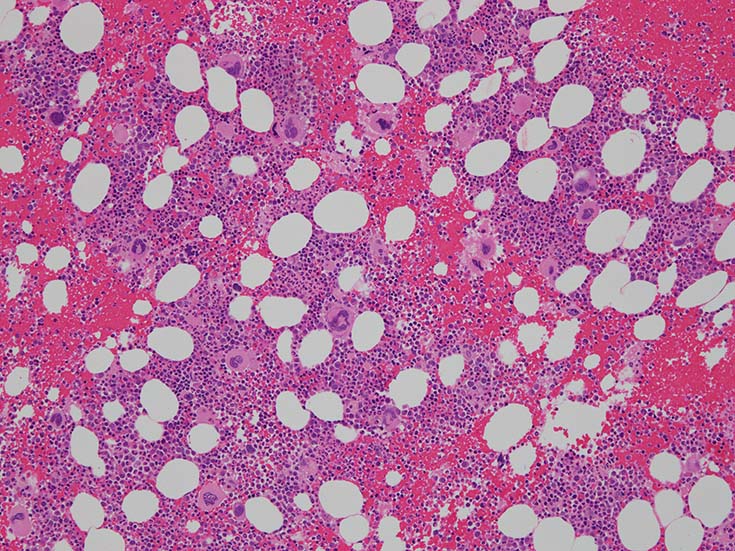

骨髄組織所見

cellularity60-70%ほどの過形成髄. ETは通常, 正形成髄から軽度の過形成髄, まれに低形成髄のこともある. 本例は軽度過形成傾向なcellularity. 巨核球数増加が目立つほか, stag-horn, cloud-likeといわれる核をもつ大型巨核球が認められる他, 小型で若い巨核球も増加している. ETでは, 連続する巨核球分化が認められる. 顆粒球系細胞増多が認められる.

Mgkの凝集所見があるが, 5-6個の緩やかな凝集で, loose clusterと呼ばれる. (Dens cluster:9個以上[数は厳密]の密なcohesiveな増殖は線維化がない場合, prefibrotic myelofibrosisの重要な所見になる)